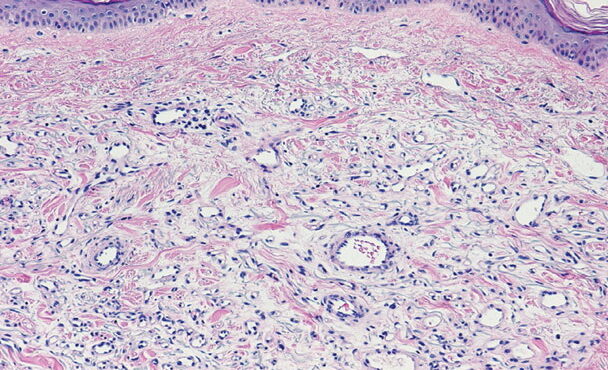

merkel-cell-carcinoma